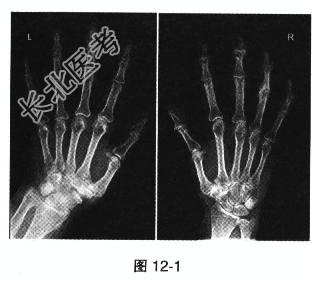

- [材料题] 患者女,56岁。双手远端指间关节膨大(图12-1),疼痛3个月,活动后加重,晨起有僵硬感,但活动数分钟后可以缓解,查体可见双手第二、三、四、五远指关节骨性膨大,有轻压痛。

- 多项选择题1.这种骨性膨大被称为

A、布夏尔结节

B、赫伯登结节

C、类风湿结节

D、杵状指

E、Gottron征

F、环形红斑